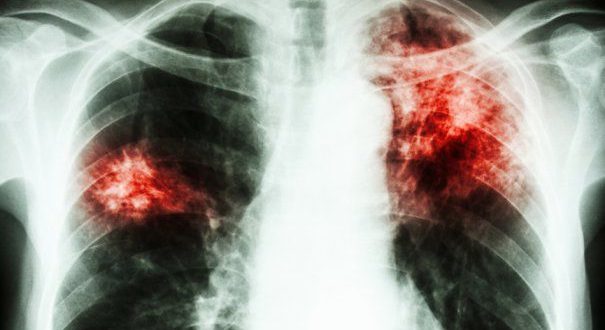

Informaţiile oficiale în acest caz al profesoarei Liceului Teoretic “George Moroianu” bolnavă de TBC provin de la urmatoarele surse abilitate: Dr. Târziu (TB Săcele), Dr. Laţcu şi Dr. Barbu (Clinica TB Braşov) şi prof. Ionuţ Tanase (director Liceul Teoretic “George Moroianu”din Săcele).

• În data de 28 decembrie, profesoara este diagnosticată cu TBC la spitalul din Floreşti, jud. Prahova.

• Copiii care au avut contact cu profesoara bolnavă, cadrele didactice şi cele auxiliare, precum şi personalul nedidactic au fost programaţi pentru investigaţii medicale la Clinica TB Braşov. Transportul copiilor la clinică a fost asigurat gratuit de către unitatea de învăţământ.

• Până astăzi (19 ianuarie) situaţia se prezintă în felul următor: La adulţi – zero depistări pozitive. La elevi există 65 de depistaţi pozitiv în urma testului IDR.

• Toate persoanele depistate pozitiv vor trece prin investigaţii medicale suplimentare: investigaţii raze, examene de sânge şi recoltări suc gastric. Aceste analize medicale vor determina în final dacă există persoane îmbolnăvite cu TBC sau nu, în afara profesoarei care a declanşat acest caz.